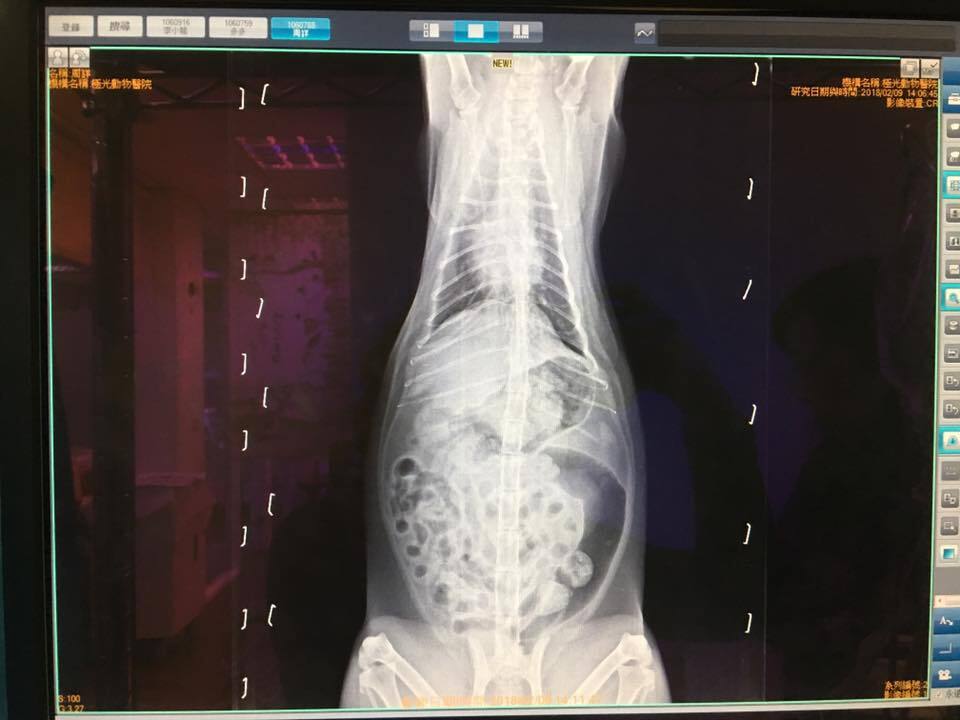

【02/09 極光看診 周詳 5.015kg/體溫39.1度】

有呼吸道感染,X光片上看到肺部沒有很乾淨;看牙齒牙周與後口應該是有口炎。口腔不舒服也容易造成免疫狀況不穩定,但周詳的口炎不一定會需要類固醇,醫師建議可做洗牙或拔牙,牙齦不會再紅也可以舒服點。所以血檢顯示慢性發炎跟呼吸道、口腔發炎都有連帶關係。X光顯示前肺、支氣管末端明顯偏白,代表有發炎累積;也看到腸道積氣很多(像脹氣),有可能造成食慾不佳,免疫狀況仍然要觀察,EOS數值高但因為同時還有其他發炎正在進行,需要先吃藥排除、驅蟲或糞檢確定沒有寄生蟲感染才能確定,建議還是要「關籠」觀察食慾精神糞便與呼吸道狀況。